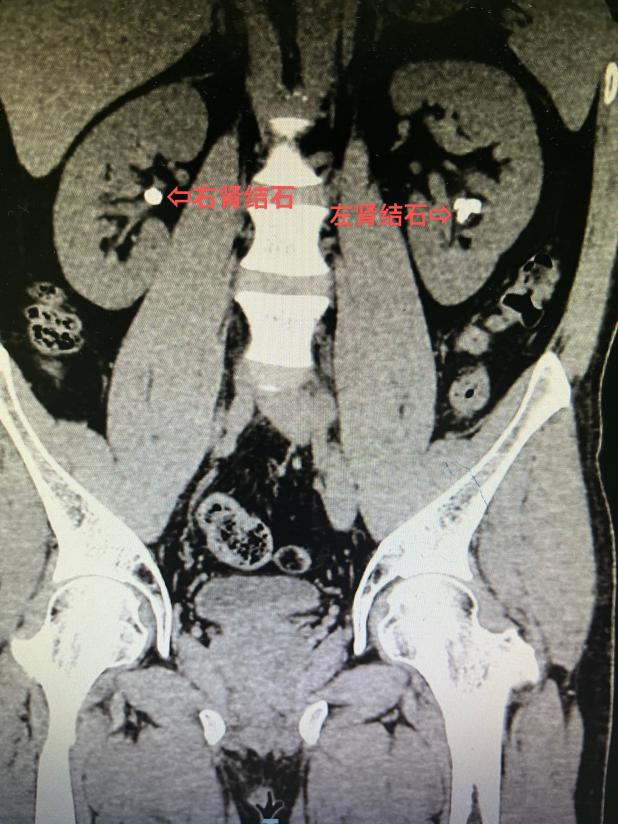

10 年前患者检查发现双肾结石,近年来反复出现腰部疼痛,在外院多次行体外冲击波碎石,未见结石排出,症状也没有改善,严重影响了工作和生活。后到 市中医医院 泌尿外科就诊,泌尿外科拓鹏飞副主任医师接诊后行 CT 显示:双肾多发结石、右侧输尿管结石。